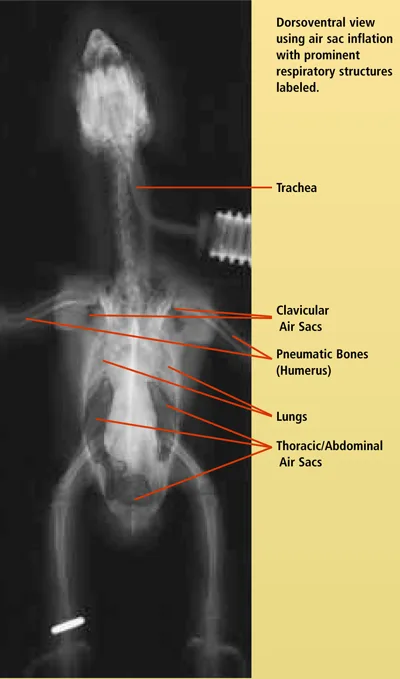

The avian respiratory system is extensive and complex. Becoming familiar with the normal presentation of respiratory anatomy through use of different imaging techniques will enhance a clinician's ability to make a diagnosis. This is the first of two articles using radiographic images and computed tomography (CT) to compare normal respiratory structures of the avian respiratory system. Note that the size of the patient dictates the size of the CT image. In this case, the patient is very small; thus, the images have become somewhat blurry with enlarging. Nevertheless, contrast is an important factor in CT imaging and the structures are quite clear. This article focuses on the body; the next part will address the head. For larger images, please click on the PDF icon at the top of the page to download the print version of the article in its entirety.